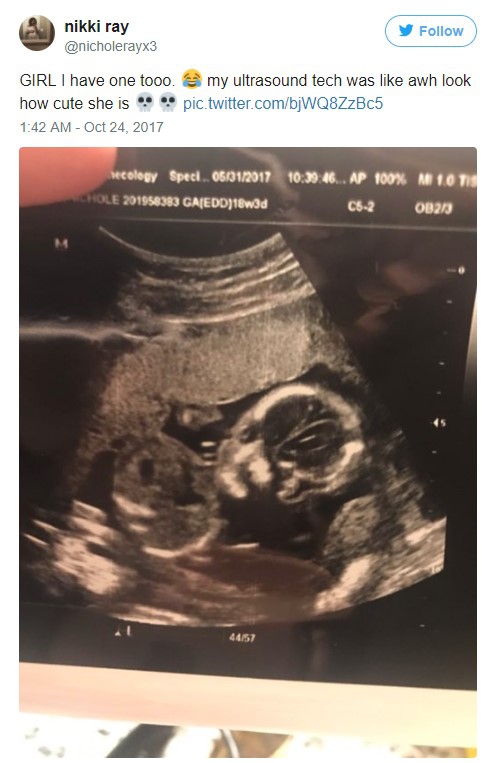

31/10/2017 17:59Mẹ trẻ Úc vừa chia sẻ ảnh siêu âm, cư dân mạng liền hốt hoảng gọi đứa trẻ trong bụng cô là “ác quỷ”

Sharni Turner, một bà mẹ trẻ tuổi người Úc vừa qua đã hạnh phúc chia sẻ bức ảnh siêu âm con lên trang Twitter của mình.

Điều đáng nói là tấm ảnh đứa bé được chụp thẳng mặt lại hiện ra giống như một chiếc đầu lâu với hố mắt đen sâu hoắm.

Sharni ban đầu cũng hơi sốc nhưng rồi cô nghĩ, đây chính là một kỷ niệm đặc biệt không phải ai cũng có được. Cô đã chia sẻ bức hình siêu âm lên mạng xã hội một cách tự hào.

Trong bài đăng, Sharni viết rất dí dỏm về bức ảnh siêu âm của con: “Bác sĩ quyết định chụp ảnh thẳng mặt cho con tôi và đó quả là một trong những thứ dễ sợ nhất mà tôi từng nhìn thấy!”

Trả lời phỏng vấn với Unilad, Sharni kể lại: “Chả hiểu sao hôm đi siêu âm đứa bé cứ ham ngủ, chẳng chịu động đậy để bác sĩ đo kích thước phát triển mới chính xác được. Chúng tôi đã thử làm hết mọi cách để đánh thức thằng bé dậy. Rồi đùng một phát, thằng bé cho chúng tôi xem gương mặt như nổi giận thế đấy. Đó là một khoảnh khắc hài hước”.

Bức ảnh siêu âm của Sharni đã được chia sẻ hơn 11,000 lần với hơn 31,000 lượt yêu thích. Bên cạnh những người hài hước “đu” theo câu đùa của Sharni, cô còn phải hứng chịu rất nhiều những bình luận khiếm nhã, độc ác khác.

Nhiều người cho rằng đứa bé trong bụng cô mang gương mặt của ác quỷ, có người bảo em bé trông chẳng khác gì chúa tể Voldemort trong Harry Potter, có người còn khuyên Sharni hãy bỏ ngay bào thai quái dị ấy đi…

Sau khi thấy hình ảnh con mình bất ngờ trở nên nổi tiếng như vậy, kèm theo nhiều lời nói ác ý, Sharni đã viết một đoạn chia sẻ cho biết: “Mặc dù hình ảnh siêu âm trông hơi quái lạ nhưng sức khỏe của em bé hoàn toàn bình thường".

"Đọc bình luận của mọi người mà tôi cười đến chảy cả nước mắt. Một số người nói những câu cay độc nhưng tôi nghĩ họ cũng chỉ đùa thôi. Tôi thật sự cảm thấy sốc khi phải đính chính rằng, tôi không hề có ý định đi phá thai hay gì cả. Dù thế nào, tôi nhất định sẽ rất hạnh phúc khi được làm mẹ của một đứa trẻ tinh quái như vậy”.

Nhiều bà mẹ hài hước khác cũng đã chia sẻ ảnh siêu âm quái lạ của con mình cùng với Sharni.